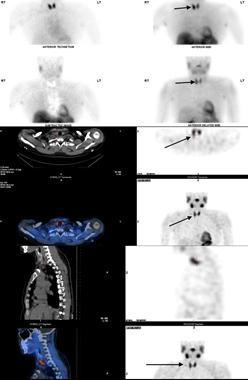

结合患者症状、查体可触及的甲状旁腺结节,初步考虑原发性甲状旁腺功能亢进症可能。进一步行甲状腺超声检查显示甲状旁腺可见结节,行单光子发射计算机断层扫描(SPECT)进行双同位素甲状旁腺扫描,发现右下甲状旁腺摄取增加,高度提示甲状旁腺腺瘤。

图1 SPECT图示建议患者行甲状旁腺切除术,术中切除右下甲状旁腺(15mm×10mm×10mm)。组织病理标本证实为甲状旁腺腺瘤。甲状旁腺切除术后,患者失眠症状很快缓解。